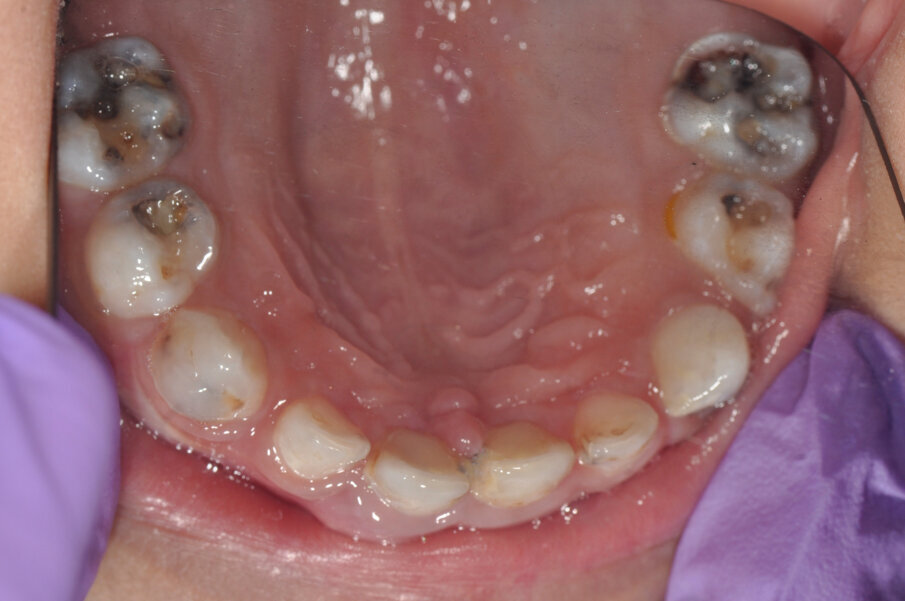

A 4-year-old girl was referred to the Children’s Dental Center in Gurgaon in India with the complaint of painful teeth when eating and the presence of unsightly maxillary anterior teeth. Clinical examination showed large carious lesions in the maxillary anterior teeth (Fig. 1). A radiographic examination showed pulpal involvement of caries in teeth #51 and 61 (Fig. 2).

Fig.1: Caries associated with the four front teeth.

Fig. 11: Preoperative situation.